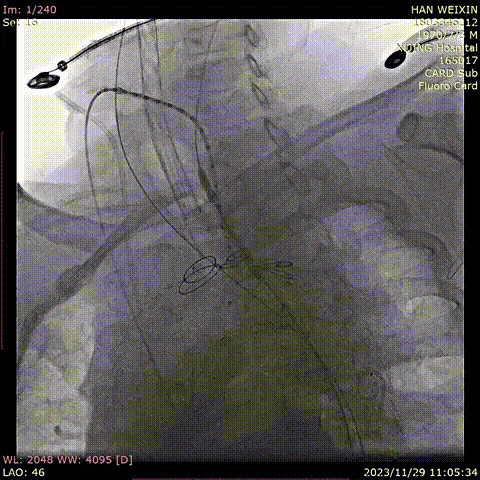

韩某,男,53岁,“查体发现主动脉弓部溃疡15天”入院,主动脉CTA提示:主动脉溃疡(弓部);2. 主动脉壁内血肿。患者高血压病史8年,最高210/130mmHg,无规律服药。

术前 CTA

术前造影

导入弓部

主体支架

释放弓部

超选左颈总动脉

超选无名动脉

并预置导丝

导入左颈总

支架并释放

导入无名动脉

超选左锁骨下

动脉

导入左锁骨下动脉

导入并释放远端支架

术前

术后

手术用时115分钟